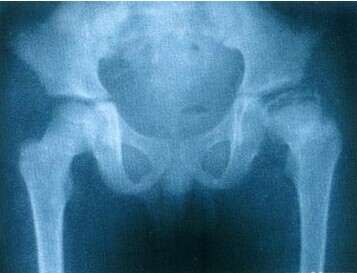

股骨头缺血性坏死晚期患者因髋关节疼痛、活动受限、股骨头严重塌陷、脱位或继发性骨关节炎,而又不适于做保留股骨头手术者,可考虑行人工关节置换。》》》做人工关节置换手术的费用贵不贵?大概要多少钱?

(1)半髋关节置换术:半髋人工髋关节置换有固定式人工股骨头、组合式人工股骨头和双动式人工股骨头。适用于病期较短、股骨头已塌陷,但髋未发生继发性骨关节炎者。术后效果满意者多,但真正属“优”者少。股骨头缺血性坏死有效不侵犯髋臼软骨者少,近年来报道指出:采用双动人工股骨头治疗股骨头缺血性坏死其结果与全髋关节置换相比,疗效较差。》》》人工关节置换手术后要注意些什么?大概多久可以正常活动?

(2)全髋关节置换术:全髋关节置换术适用于有症状的股骨头缺血性坏死晚期患者,目前已成为临床治疗的标准手术之一。过去多采用骨水泥固定全髋关节,但长期随诊,其结果不理想,特别是髋臼的松动率高。而这些报道都是十余年前所做的手术,所用材料与手术技术与今天有较大的差别。